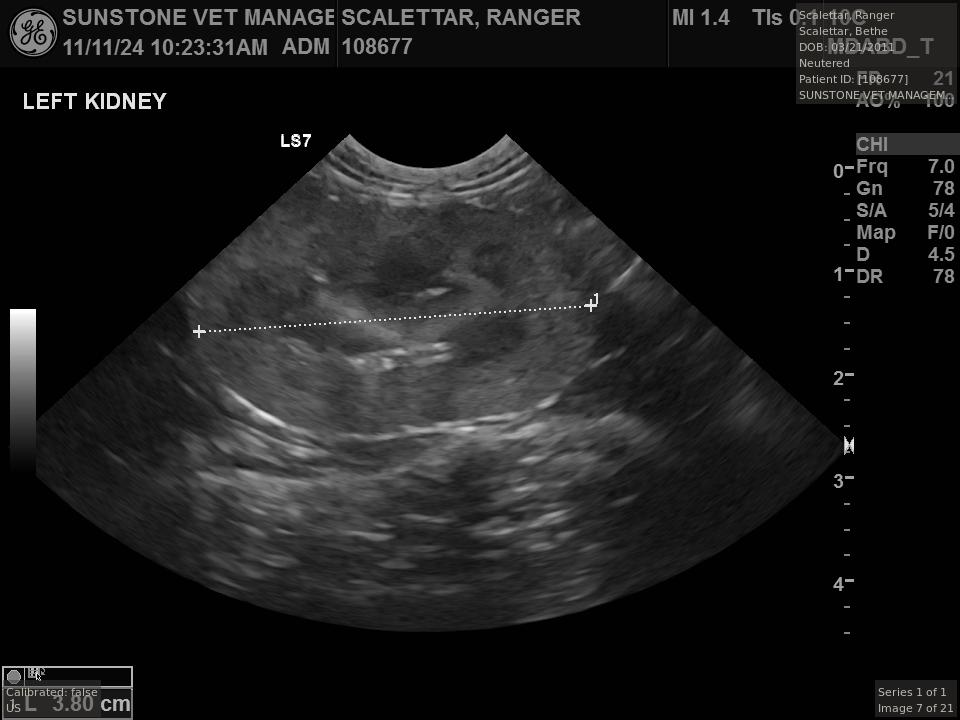

The veterinarian generated a series of images showing different organs and substructures by

changing the position and orientation of the ultrasound transducer. The images were collected

in a defined order, which is repeated from patient to patient, ensuring that nothing is missed. In

Ranger's case, the sonographer collected about twenty images during an examination that

lasted about fifteen minutes.

The sonographer stated that Ranger's ultrasound images were largely normal for an older cat. In particular, they show changes in the kidneys that are commonly noted in geriatric cats and that reflect a risk for the development of chronic kidney disease. However, the images did not show any significant abnormalities in Ranger's stomach, intestines, and associated lymph nodes. Nonetheless, the results did not rule out recurrence of Ranger's small cell lymphoma.